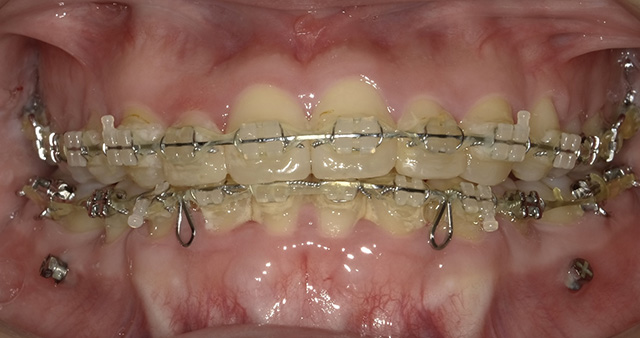

歯の表面にワイヤーとブラケットと呼ばれる固定装置を装着して歯列を整えていく方法で、歯列矯正の中で最も広く行われています。数ミリ単位で歯の移動が可能です。

最近では、歯と同じ色の目立ちにくいブラケットやワイヤーが揃っており、素材を選ぶことで目立ちにくくすることが可能です。